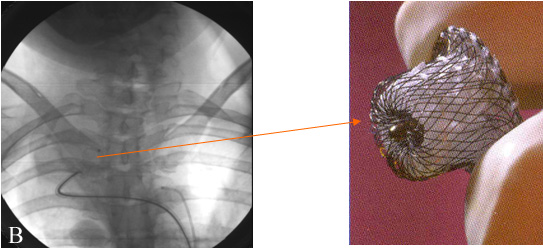

26.12.2003г. проведена эндоваскулярная операция — закрытие аневризмы с помощью устройства «Amplatzer duct occluder» (рис.7 ).

Описание устройства: Amplatzer duct occluder представляет собой устройство, позволяющее закрывать большие открытые артериальные протоки (диаметром от 3 до 14 мм). Сам окклюдер состоит из нитиноловых нитей, покрытых изнутри дакроном. Размер окклюдера подбирался с расчетом, чтобы проксимальный конец окклюдера прикрывал полость аневризмы непосредственно из аневризматического мешка, а дистальный — выступал в просвет правой позвоночной артерии. Для имплантации окклюдера использовалась специальная доставляющая система. Доставляющая система состоит из следующих структурных элементов: длинного интродьюссера, дилататора, толкателя и загрузочного устройства.

В полости аневризмы произвели раскрытие дистального отдела окклюдера с последующим низведением к границе проксимального отдела аневризматического мешка и интактной правой позвоночной артерии. Выполнялась ангиография, которая подтвердила правильное расположение окклюдера в полости аневризмы и наличие незначительного резидуального сброса крови через каркас устройства. Затем произвели раскрытие остальной части окклюдера. После имплантации окклюдера выполнили контрольную ангиографию, которая показала отсутствие антеградного заполнения полости аневризмы и наличие незначительного сброса крови через каркас устройства. Наличие резидуального сброса через каркас окклюдера не свидетельствует о неполном закрытии дефекта, так как процесс тромбообразования на устройстве может занимать несколько дней. Затем произвели отцепление окклюдера от катетера- толкателя (рис.7).

Рис.7 Закрытие аневризмы имплантацией устройства «Amplatzer» для закрытия открытого артериального протока .

В) устройство «Amplatzer» для закрытия открытого артериального протока .